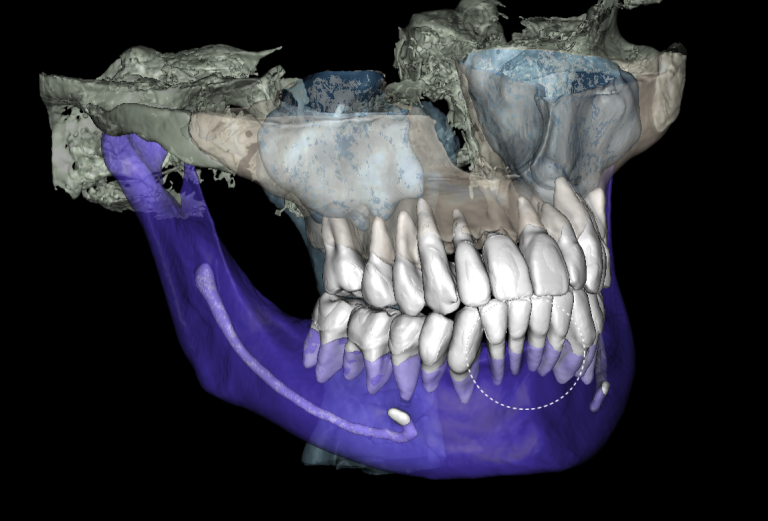

The “Third Molar Report” is a tool created by Diagnocat AI, it creates an optimal 3D visualization which helps to assess the position of the roots of the third molars relative to the roots of adjacent teeth and the floor of the maxillary sinus.

Teeth 18 (Universal 1) and 28 (Universal 16) were removed with minimal surgical trauma and without causing damage to the maxillary sinuses.